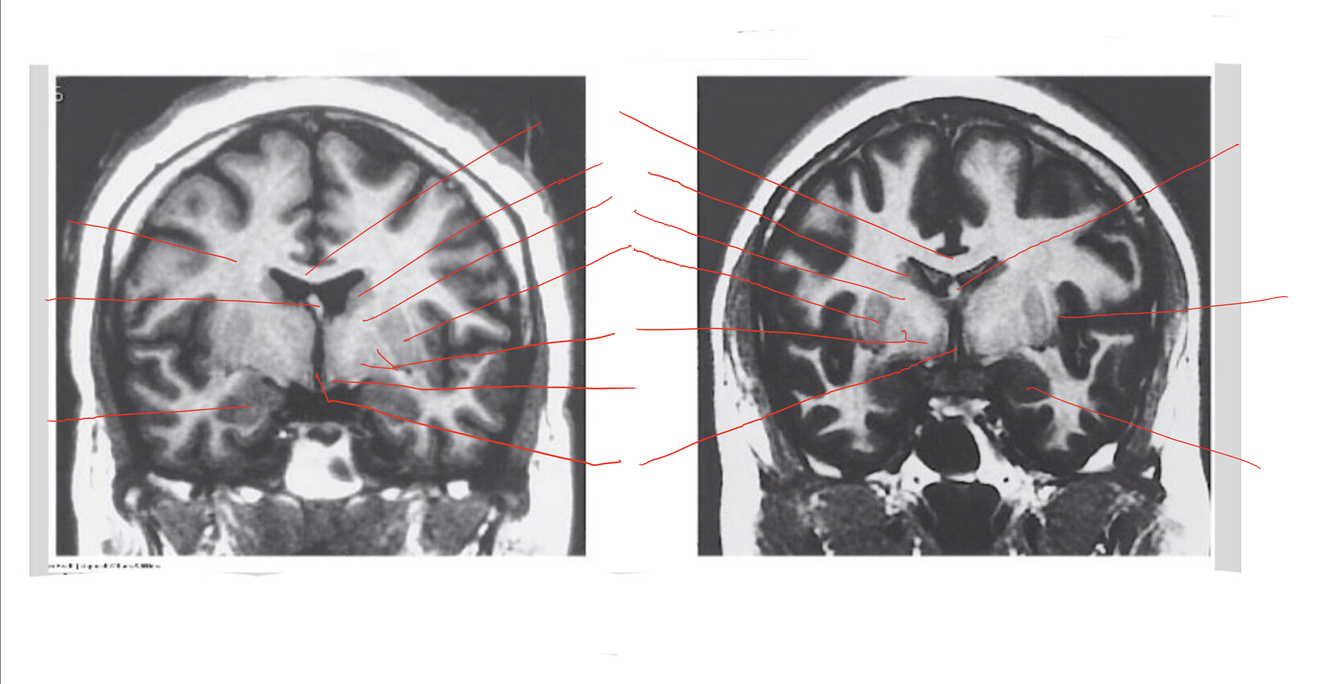

The structure indicated by the red line is?

The structure indicated by the red line is? BONUS: SYMPTOMS IF THERE IS A LESION

motor problems